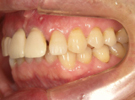

50代女性

![]() |

治療前 |

||

治療中。仮歯。 左上の奥にインプラント埋入。 噛みあわせ治療を行いました |

治療後 全体の歯で食事がおいしくできるようになったと喜んでおられました。 |